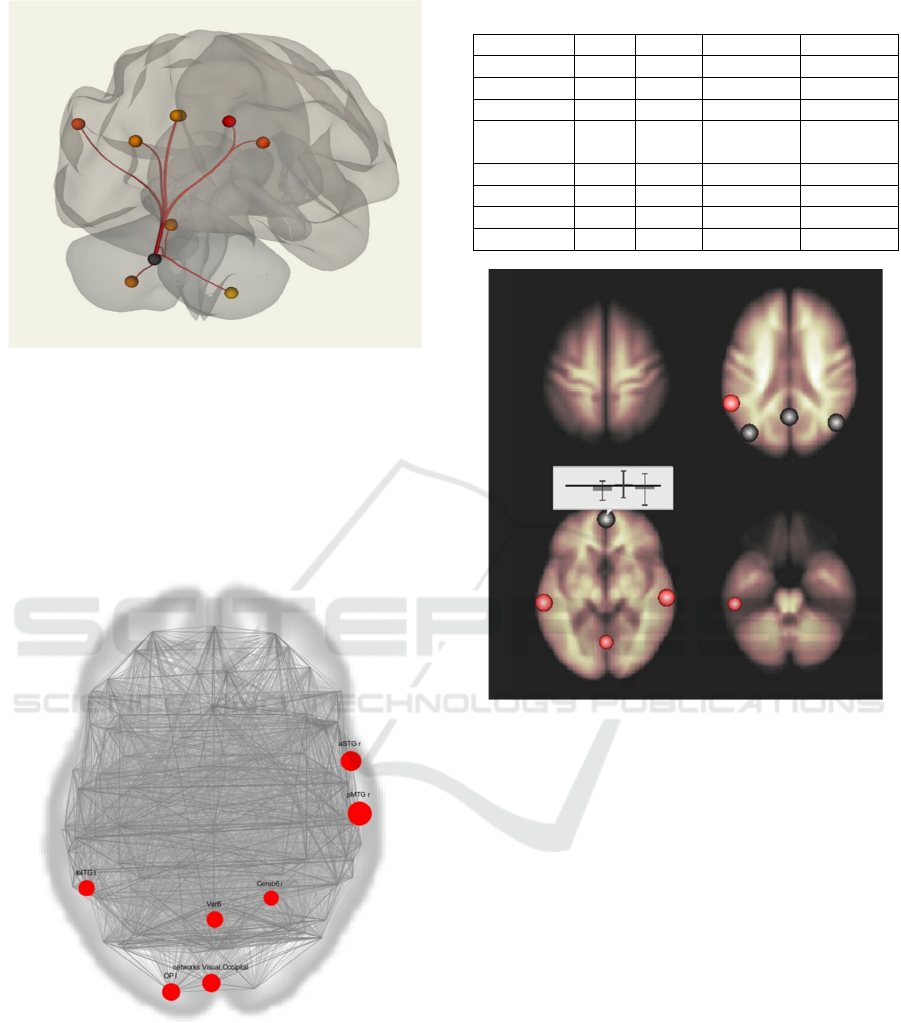

Analyzing the functional MRI data, when

Region of interest - cerebellar area. Demonstrated

positive FC with right and left hemisphere of the

cerebellum (8 area), the vermis cerebellum, the

precuneus, angular gyri and posterior divisions of the

cingulate gyrus (part of the default mode network)

(Figure 1).

When performing an analysis based on graph

theory with global efficiency assessment after a

course of leech therapy, stable functional

relationships between the middle temporal gyrus

(posterior, right), upper temporal gyrus (anterior,

right) and lower temporal gyrus were determined

comparing to the results of the study before the start

Analysis of Functional Connectivity When using Complementary Methods of Treatment in Patients with Asymptomatic Carotid Stenosis

Figure 1: Cerebellar network. Intergroup comparison.

of treatment (temporal-occipital departments, left),

lingual network, visual network, cerebellar vermi,

zone 6 of the right hemisphere of the cerebellum, pole

of the occipital lobe. At the same time, the degree of

severity of activation of the lingual network (upper

and lower frontal gyrus on the right) was decreased

(Figure 2, Table 1).

Figure 2: Maps of functional connectivity. Graph theory

results.

There was an increase of the negative functional

connections of MPFC with the left middle frontal

gyrus and a weakening of the negative functional

connections of MPFC with the right parahippocampal

gyrus p<0.001 (Figure 3).

Table 1: The degree of activations severity.

Figure 3: Intragroup comparison of the subjects before and

after a course of treatment. The changes that occur after

treatment are shown. Activation sites combined with

anatomical images of the head brain regions positively

functionally associated with MPFC are mapped in red, and

negatively functionally associated with MPFC are mapped

in blue (p<0,001).